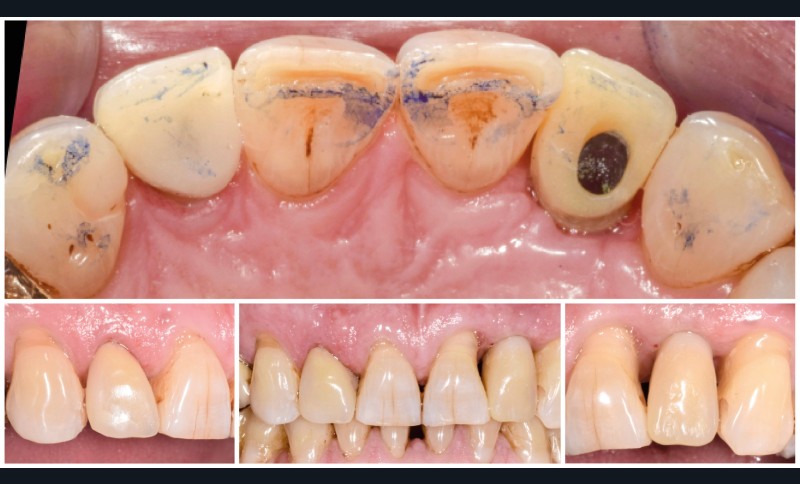

Situation initiale

Un patient de 62 ans se présente en consultation afin de réaliser les coiffes prothétiques des dents 12 et 22. La 12 présente une restauration par prothèse transitoire non adaptée. Un implant au niveau de la 22 a été posé par un autre praticien selon une technique chirurgicale en deux temps. Le praticien a adressé le patient pour la réalisation prothétique. L’option de bridge collé cantilever mono ailette n’avait pas été retenue ou proposée selon une technique chirurgicale en deux temps. Le patient souhaite rétablir l’esthétique et la fonction de ces deux dents uniquement.